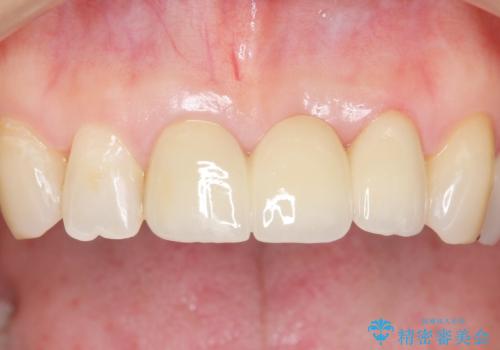

前歯のレジン前装冠(保険内)によるブリッジは、金属で裏打ちされており透明感がなく不自然で、ポンティックも必要以上に長く作られていました。

古いブリッジと金属の土台を除去し、ファイバーコア(金属を使わない強くてしなやかな土台)を植立したのち、オールセラミックのブリッジによる補綴治療を行いました。。